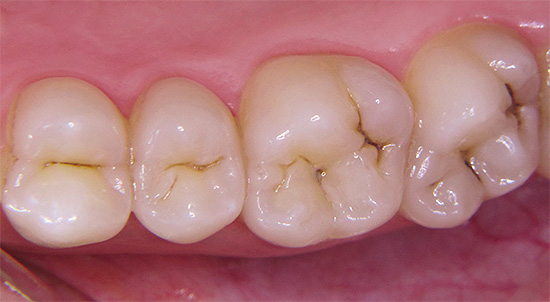

La carie durante la gravidanza si presenta nel suo insieme più spesso che in altri periodi della vita di una donna, e spesso si verifica molto attivamente in questo momento, a volte anche in forma acuta. Le preoccupazioni delle future mamme sui possibili effetti della carie sul feto, così come le paure circa la possibilità di trattare i denti in un periodo così cruciale, sono abbastanza comprensibili.

In alcuni casi, durante la gravidanza, la carie inizia solo il suo lavoro distruttivo (e molti cercano di aspettare questa volta), e le conseguenze più evidenti e sensibili del danno ai denti attendono una donna dopo il parto.

La carie durante la gravidanza è in gran parte dovuta agli stessi motivi dei casi con altre categorie di pazienti: scarsa igiene orale, abbondanza di snack durante il giorno e passione per i dolci.

- Una diminuzione della concentrazione di calcio e composti del fluoro sia nella saliva che nel sangue a causa di un certo consumo per le esigenze di un embrione in via di sviluppo. Allo stesso tempo, il calcio non viene consumato dai denti stessi, come molti credono in modo errato. Ma la rimineralizzazione dello smalto e il suo rafforzamento, che si verificano sempre in altri periodi a causa dell'azione della saliva, durante la gravidanza possono rallentare o addirittura arrestarsi. Di conseguenza, lo smalto diventa debolmente mineralizzato e viene più facilmente danneggiato dai rifiuti acidi prodotti dai batteri.